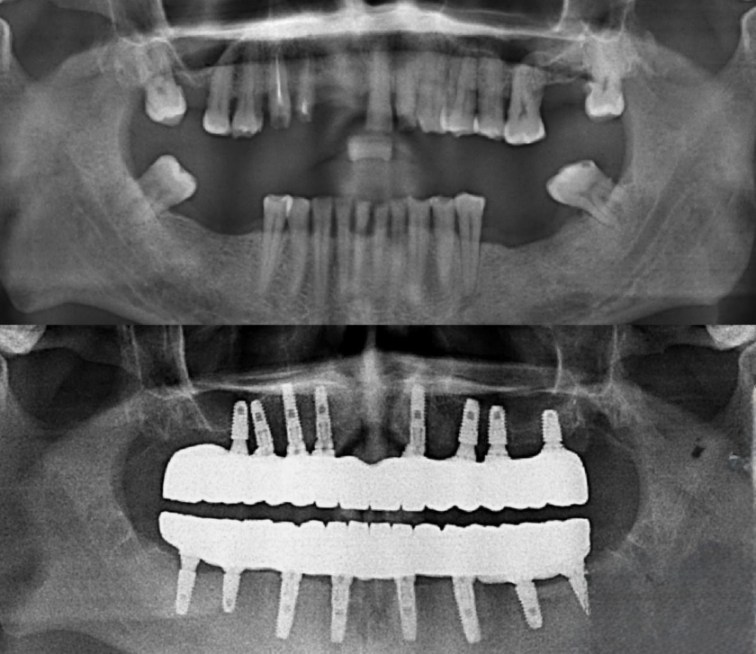

All-on-8-Zahnimplantate in der Türkei repräsentieren eine innovative Vollkieferrestauration, bei der acht Titanimplantate strategisch im Kieferknochen platziert werden. Diese Methode ermöglicht es, einen kompletten Zahnbogen mit einer festsitzenden Brücke zu versorgen, ohne dass herausnehmbare Prothesen erforderlich sind. Die acht Implantate verteilen die Kaubelastung gleichmäßig über den gesamten Kieferknochen und fördern dabei die natürliche Osseointegration.

All on 8 implantate bieten durch ihre Anzahl eine überlegene Stabilität im Vergleich zu All-on-4 oder All-on-6 Systemen. Die Zahnrestauration in der Türkei erfolgt nach modernsten Standards und gewährleistet optimale Stabilität des gesamten Zahnbogens. Diese Technologie verhindert effektiv den fortschreitenden Knochenschwund und stellt die natürliche Gesichtsstruktur wieder her.

Die umfassende Erstuntersuchung beinhaltet digitale Röntgenaufnahmen, 3D-Bildgebung (CBCT) und medizinische Anamnese. Fotos der aktuellen Zahnsituation werden erstellt und Behandlungsoptionen besprochen. Dieser Termin dauert etwa 90 Minuten.

Mithilfe digitaler Designsoftware wird die optimale Implantatposition bestimmt. Die Auswahl der Implantatmarke erfolgt nach individuellen Anforderungen und anatomischen Gegebenheiten. Ein detaillierter Behandlungsplan wird erstellt.

Die chirurgische Platzierung aller acht Implantate erfolgt in einer Sitzung. Präzise Bohrprotokolle gewährleisten optimale Primärstabilität. Das angestrebte Drehmoment liegt zwischen 35 und 45 Ncm für eine sofortige Belastung.